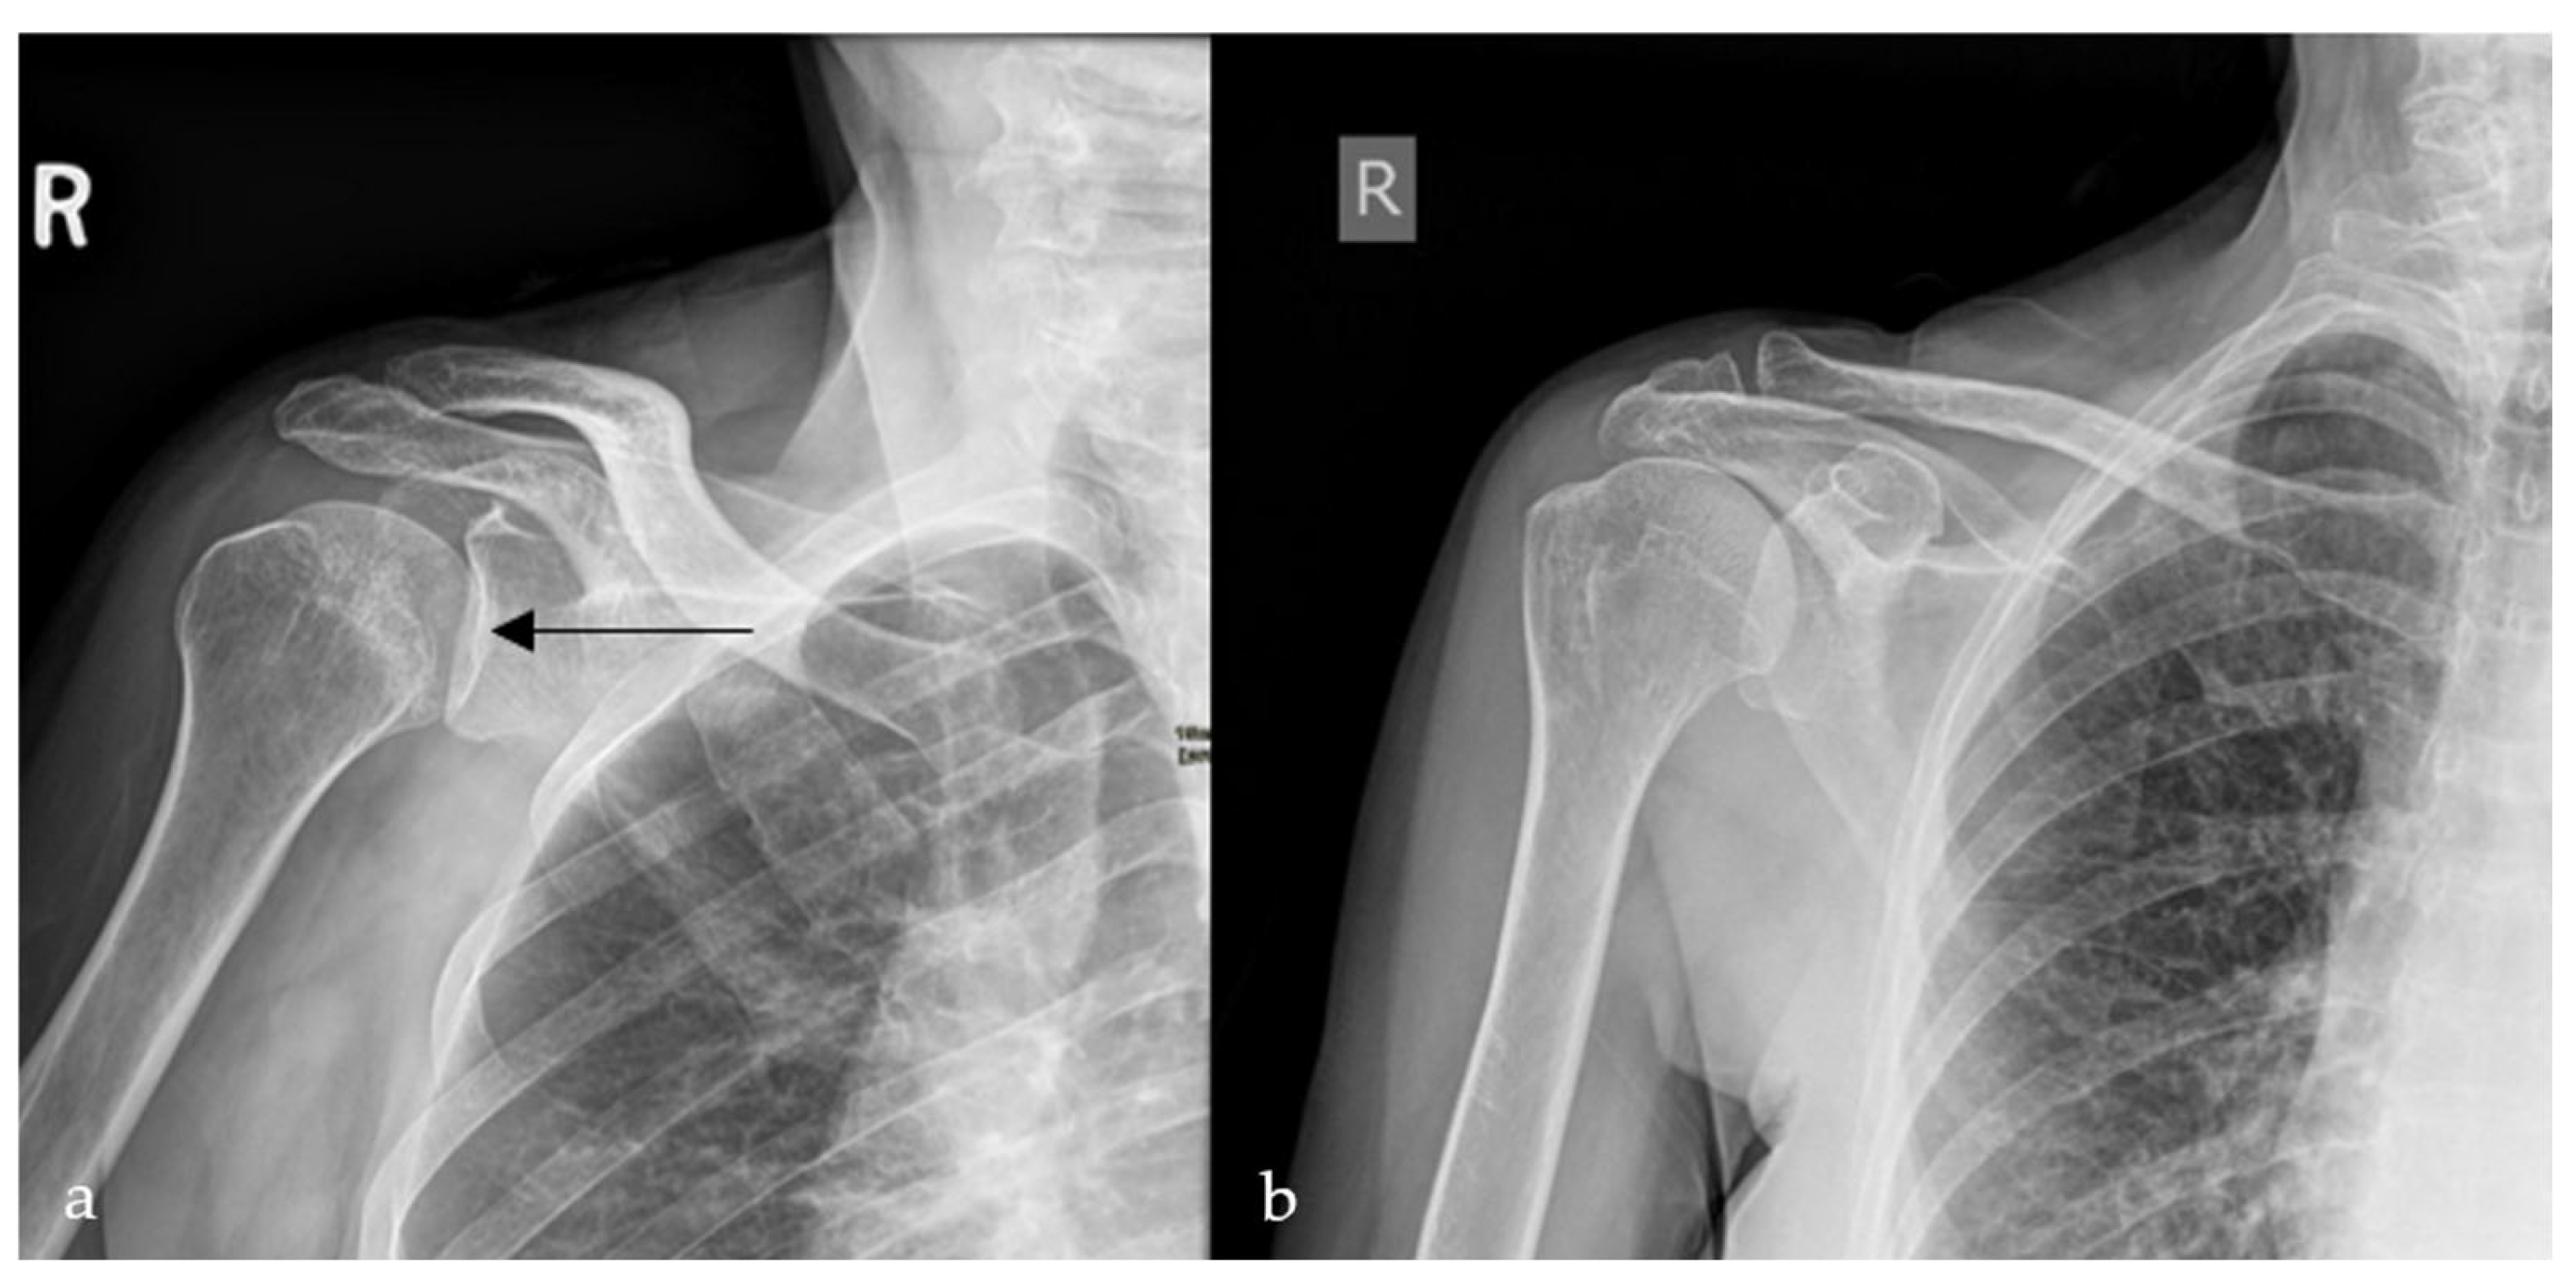

2.4. Loss of Half-Moon Overlap Sign

- Gor, D. The Trough Line Sign. Radiology 2002, 224, 485–486. [Google Scholar] [CrossRef] [PubMed]

- Sanders, T.; Jersey, S. Conventional Radiography of the Shoulder. Semin. Roentgenol. 2005, 40, 207–222. [Google Scholar] [CrossRef]

| AVN Crescent Sign | Radiograph/MRI | Stage III avascular necrosis of femoral head | Highly specific for subchondral collapse | Predicts imminent structural failure of femoral head; crucial for staging and surgical planning. |